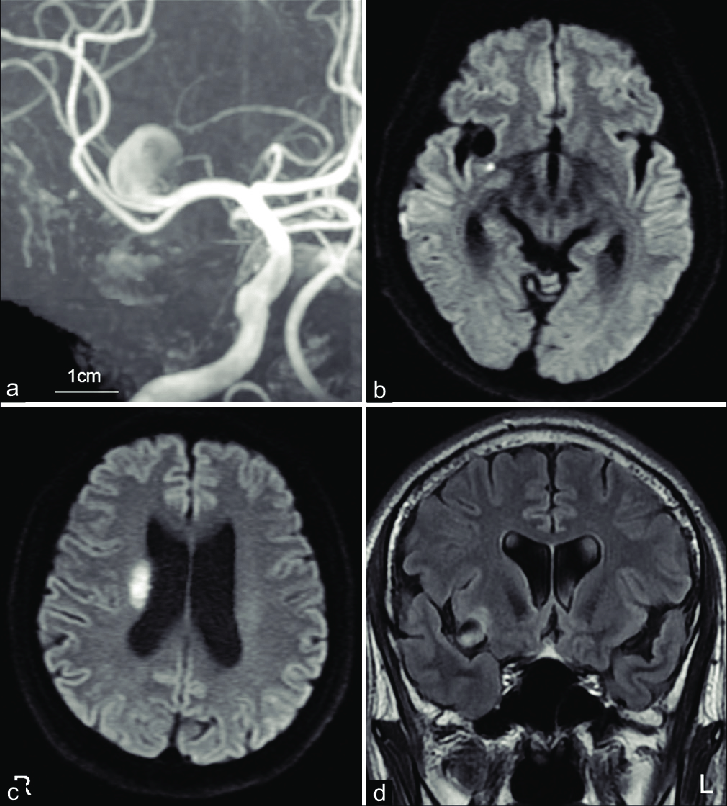

В диффузионно-взвешенном режиме может фиксироваться ограничение диффузии в виде участков гиперинтенсивного сигнала, соответствующих зонам ишемического повреждения, если исследование выполнено в первые 24 часа после эпизода.

В ангиографическом режиме без контраста выявляется изменение просвета магистральных артерий, включая их стенозы или резкие изгибы, которые могут провоцировать транзиторные ишемические атаки.

- Очаги ишемических изменений, регистрируемые в диффузионно-взвешенном режиме, что позволяет выявить зоны ограниченной диффузии при остром нарушении кровообращения.

- Состояние артериального русла при МР-ангиографии, что позволяет выявить стенозы, извитость или другие сосудистые аномалии, являющиеся причиной транзиторных атак.